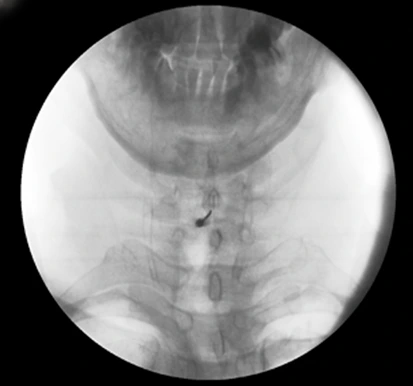

CI(C-arm Intervention) 주사 치료는,

쉽게 말하면 경추 경막외 주사 치료입니다.

C-arm이라는 특수 영상 장치로 실시간으로 보면서,

염증이 생긴 경막 외 공간에 정확하게 약물을 주입하는 방법이에요.

[환자분의 목에 CI 주사 치료를 하는 장면입니다. C-arm이라는 장비를 통해 보고 있는 덕에 더 확실하게 병변 부위를 찾아 놓을 수 있죠.]